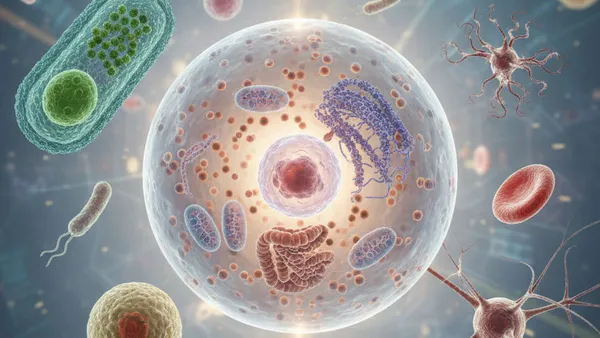

The Secret World of Cells

What if you are a walking city of 30 trillion tiny, living robots?

Chemical Cytology: The Molecules of Life

What hidden chemicals are secretly running the microscopic city inside you?